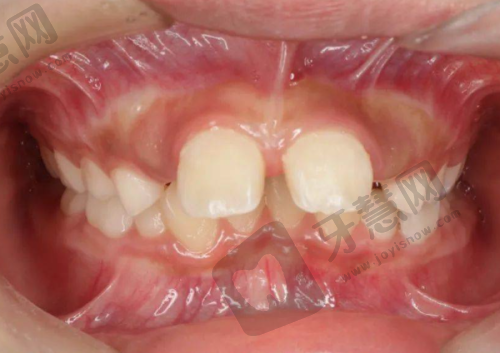

全好口腔热门的牙齿矫正项目

特别多人希望拥有整齐牙齿,不仅为美观,更为口腔健康,全好口腔的牙齿矫正项目是热门选择。它提供多种牙齿矫正方法,满足不同患者需求。传统金属托槽矫正价格相对亲民,几千元起,通过在牙齿上粘贴金属托槽,利用钢丝力量移动牙齿达到矫正目的,技术成熟,矫正成效稳定,适合牙齿排列不齐较重度的患者。隐形矫正近年来受欢迎,采用透明矫正器,几乎看不出来,不影响美观,佩戴舒适,患者可自行摘戴,方便清洁口腔,价格相对较高,一万元起。全好口腔医生根据患者牙齿状况和需求推荐合适矫正方法,矫正过程中定期复查,根据牙齿移动情况调整方案,还为患者提供口腔护理建议,帮助度过矫正期。特别多患者在全好口腔矫正后,牙齿变整齐,自信心增强。